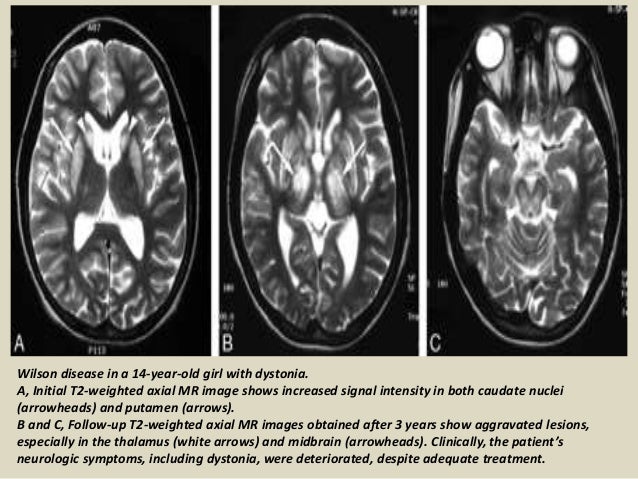

Presentation1; Radiological Imaging Of Wilson Disease.

Presentation1; radiological imaging of wilson disease. www.slideshare.net

presentation1 radiological

MR Imaging Of The Brain In Wilson Disease Of Childhood: Findings Before

MR Imaging of the Brain in Wilson Disease of Childhood: Findings Before www.ajnr.org

wilson disease brain mr findings imaging child correlation clinical childhood treatment before ajnr fig